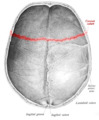

Sobo 1909 46 - Coronal suture.png

Superior view of the skull. ("Coronal suture" in red.)